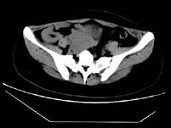

- 单项选择题女,24岁, 近日尿频明显,CT检查如图所示, 最可能的诊断是 ( )

A、膀胱癌

B、子宫肌瘤

C、卵巢癌

D、盆腔纤维瘤

E、卵巢囊肿